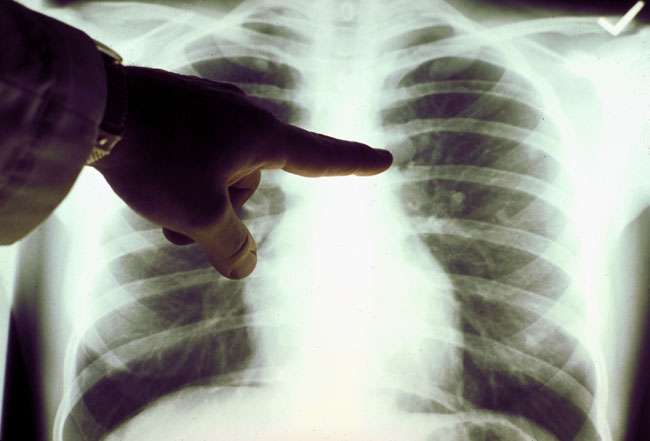

Ծայրահեղ վատ պայմաններում ապրող այս ընտանիքի զավակի` 12 ամյա Նարեկ Պանոսյանի սրտի և թոքի արանքում ուռուցք են հայտնաբերել...ծնողներն անճարությունից նույնիսկ իրենց կյանքին վերջ տալու փորձեր են արել...սարսափելի է....